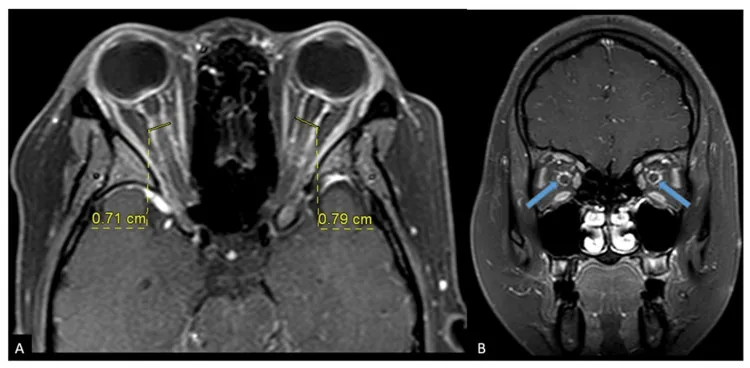

MRIが診断の要である。ガドリニウム造影・脂肪抑制T1強調画像で以下の所見を確認する。

ONとの鑑別においては、ONでは視神経自体が増強するのに対し、OPNでは視神経鞘周囲が増強する点が重要である。ただし、tram-track signはOPN特異的ではなく、視神経鞘髄膜腫・サルコイドーシス・白血病でも出現しうる。CTは軟部組織解像度が劣るため診断には不十分である。

Tanakaら(2022)は内頸動脈傍眼動脈瘤に対するフローダイバーター留置後にOPNを発症した2症例(49歳・57歳女性)を報告した。術後に視野障害が出現し、MRI STIR冠状断でdoughnut signを確認した。ステロイドパルス療法で改善を得た。術前STIR冠状断評価の重要性が強調された。6)